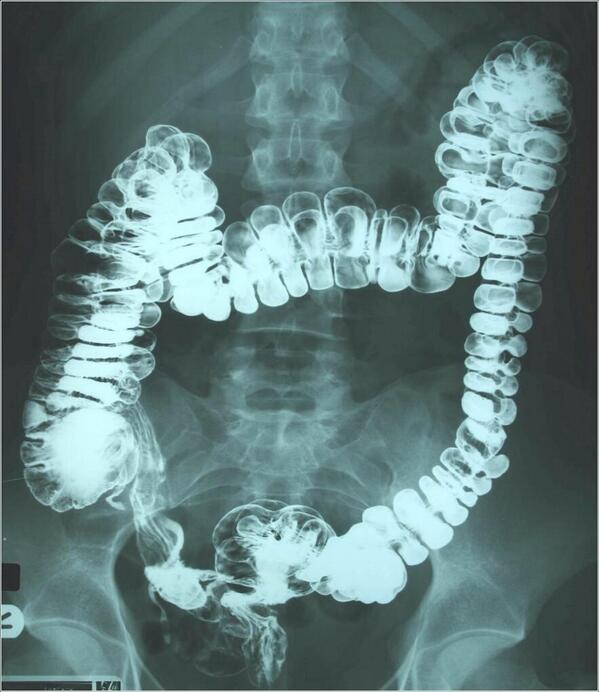

٢- سرطان القولون..

وهو رقم 5 في المملكة على مستوى النساء والرجال

أعراض السرطان خفيه أحيانا ويمكن تأويلها لأسباب أخرى أو يكون التشخيص متأخر

تبدأ الفحوصات عند 50 سنه وتكون على شكل..

فحص الدم في البراز..

ولكن هذا الفحص لا يحدد موقع او نوعية هذا الدم وهل هو حميد او خبيث المنشأ..

منظار القولون..

وهو الفحص الكامل حيث يظهر شكل الأنسجة ووجود الأورام وموقعها مع إمكانية أخذ عينة في نفس الوقت في حالة وجود أي أورام..

وفي حالة وجود تاريخ مرضي او نزول دم من فتحة الشرج على المريض مراجعة الطبيب للتأكد من السبب..

منظار القولون لا يحتاج إعاده ل 10سنوات بعده